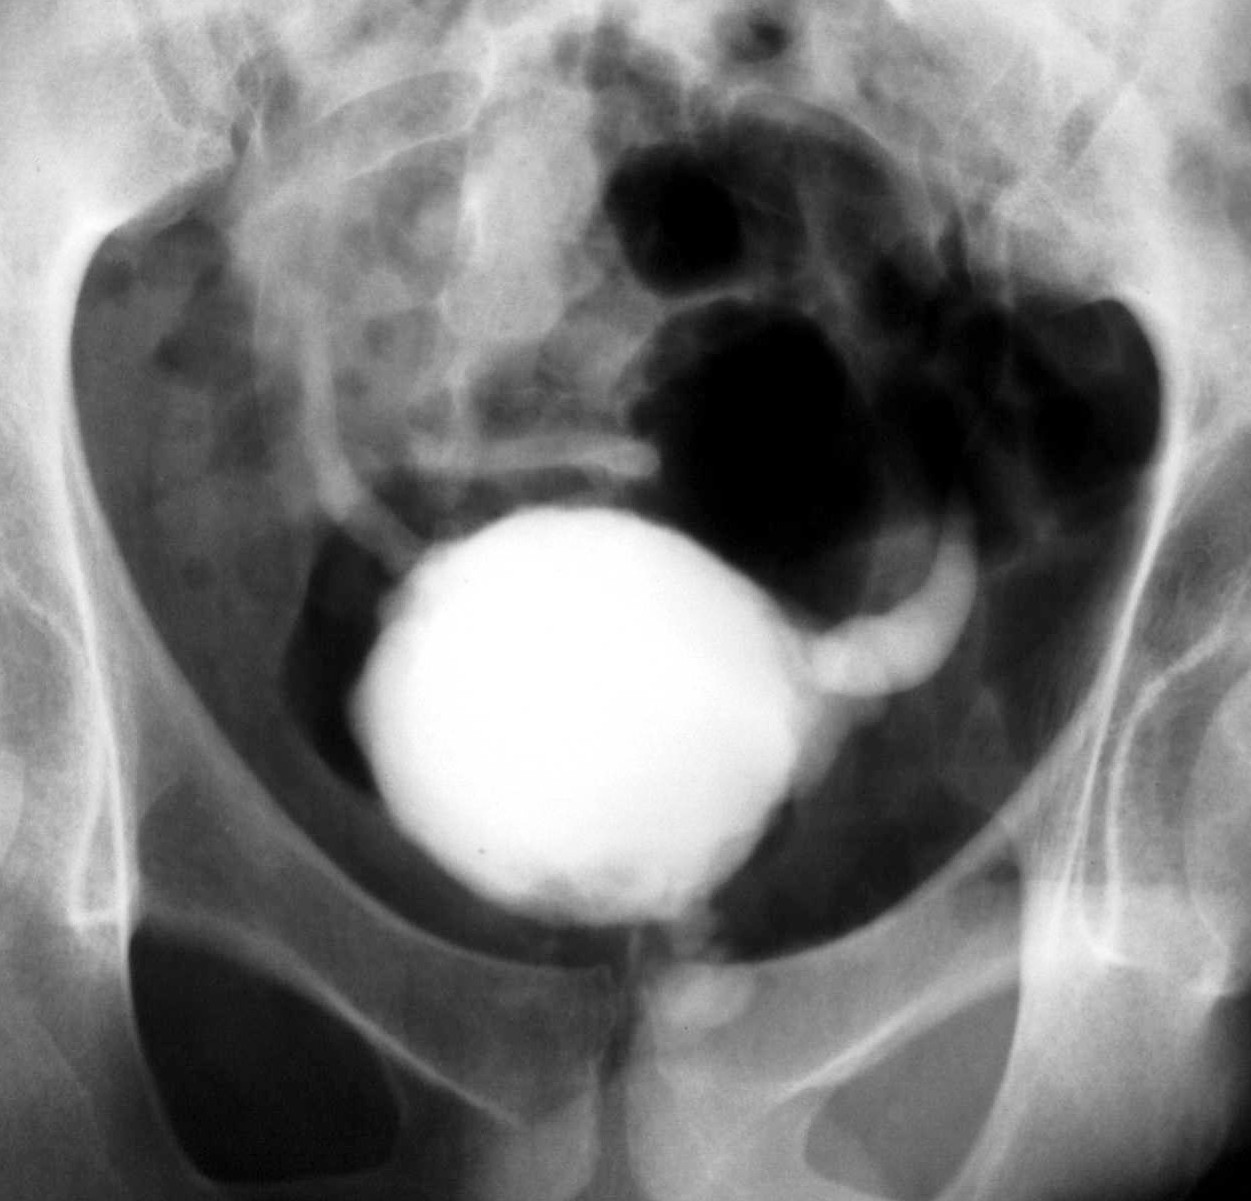

- Figure 7: Cystogram showing a small, contracted bladder due to TB cystitis